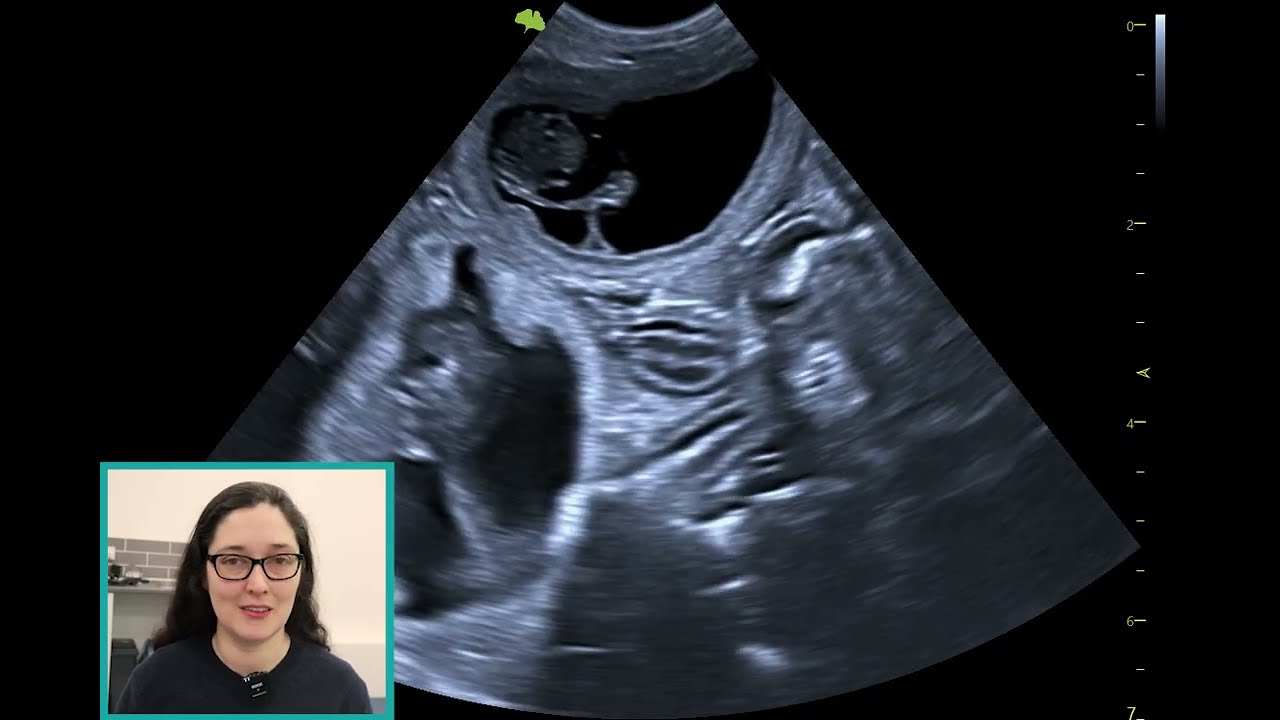

Ultrasound in Emergency & Critical Care Patients

Описание: Ultrasound in Emergency & Critical Care Patients

Speaker - Rosie Ellis DVM PgC(DI) MSc BA